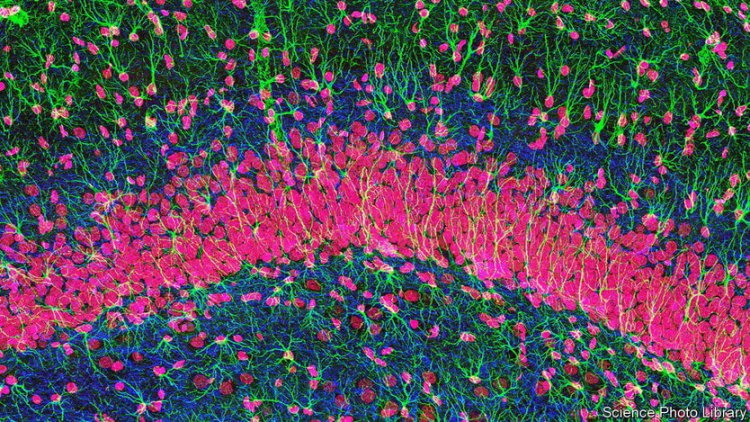

Είναι όμως οι πρόσφατα ανακαλυφθείσες ιδιότητες των αστροκυττάρων που συναρπάζουν τους ερευνητές. Αυτά τα κύτταρα «χιονονιφάδες» διαθέτουν έλικες, κάθε μία από τις οποίες καταλήγει σε ένα «πόδι». Κάθε αστροκύτταρο ελέγχει μια δική του περιοχή, και όλα μαζί σχηματίζουν ένα «τρισδιάστατο μωσαϊκό» στον εγκέφαλο.

Τα «πόδια» των αστροκυττάρων εντοπίζουν και περιβάλλουν τις συνάψεις, γεγονός που τους επιτρέπει να «κρυφακούν» την ανταλλαγή πληροφοριών μεταξύ των νευρώνων και, στη συνέχεια, ενισχύοντας ή αποδυναμώνοντας συγκεκριμένες συνάψεις, να ελέγχουν τους υπολογισμούς που γίνονται μέσα στα νευρωνικά δίκτυα. Υπάρχουν πλέον αδιάσειστα στοιχεία ότι τα αστροκύτταρα διαδραματίζουν κρίσιμο ρόλο στο, σχηματισμό της μνήμης, ιδίως στον ιππόκαμπο, ο οποίος παγιώνει τις βραχυπρόθεσμες μνήμες σε μακροπρόθεσμες.

Βιοψίες δείχνουν ότι (ανάλογα με την περιοχή του εγκεφάλου) τα αστροκύτταρα ρυθμίζουν το 50% έως 90% των συνάψεων του ανθρώπινου εγκεφάλου. Η ανάμειξη των αστροκυττάρων είναι επομένως ο κανόνας και όχι κάποια εξαίρεση. Ετσι, πολλοί ερευνητές μιλούν πλέον ανοιχτά για την «τριμερή σύναψη» ως την τυπική σύναψη στον εγκέφαλο. Είναι αυτή η σύνθεση τριών στοιχείων που μετατρέπει μια σύναψη σε «τρανζίστορ», με το ένα μέρος (το αστροκύτταρο, το ισοδύναμο της σύνδεσης “βάσης” του τρανζίστορ) να ρυθμίζει τη διέλευση των σημάτων μεταξύ των άλλων δύο (των νευρώνων, τα ισοδύναμα του μέρους που συλλέγει, και του μέρους που εκπέμπει σήματα).

Τα αστροκύτταρα δεν παρεμβαίνουν απλώς στη δράση των νευρώνων, αλλά είναι και σε θέση να εκτελούν τους δικούς τους υπολογισμούς. Στα «σύνορα» των περιοχών δύο αστροκυττάρων, οι έλικές τους μπορούν να συνδεθούν από άκρη σε άκρη, επιτρέποντάς τους να σχηματίσουν δίκτυα σχεδόν εξίσου πολύπλοκα με εκείνα των νευρώνων. Αυτό τους επιτρέπει να επικοινωνούν χρησιμοποιώντας παλμούς ιόντων ασβεστίου που περνούν από την έλικα του ενός κυττάρου στην έλικα του άλλου.